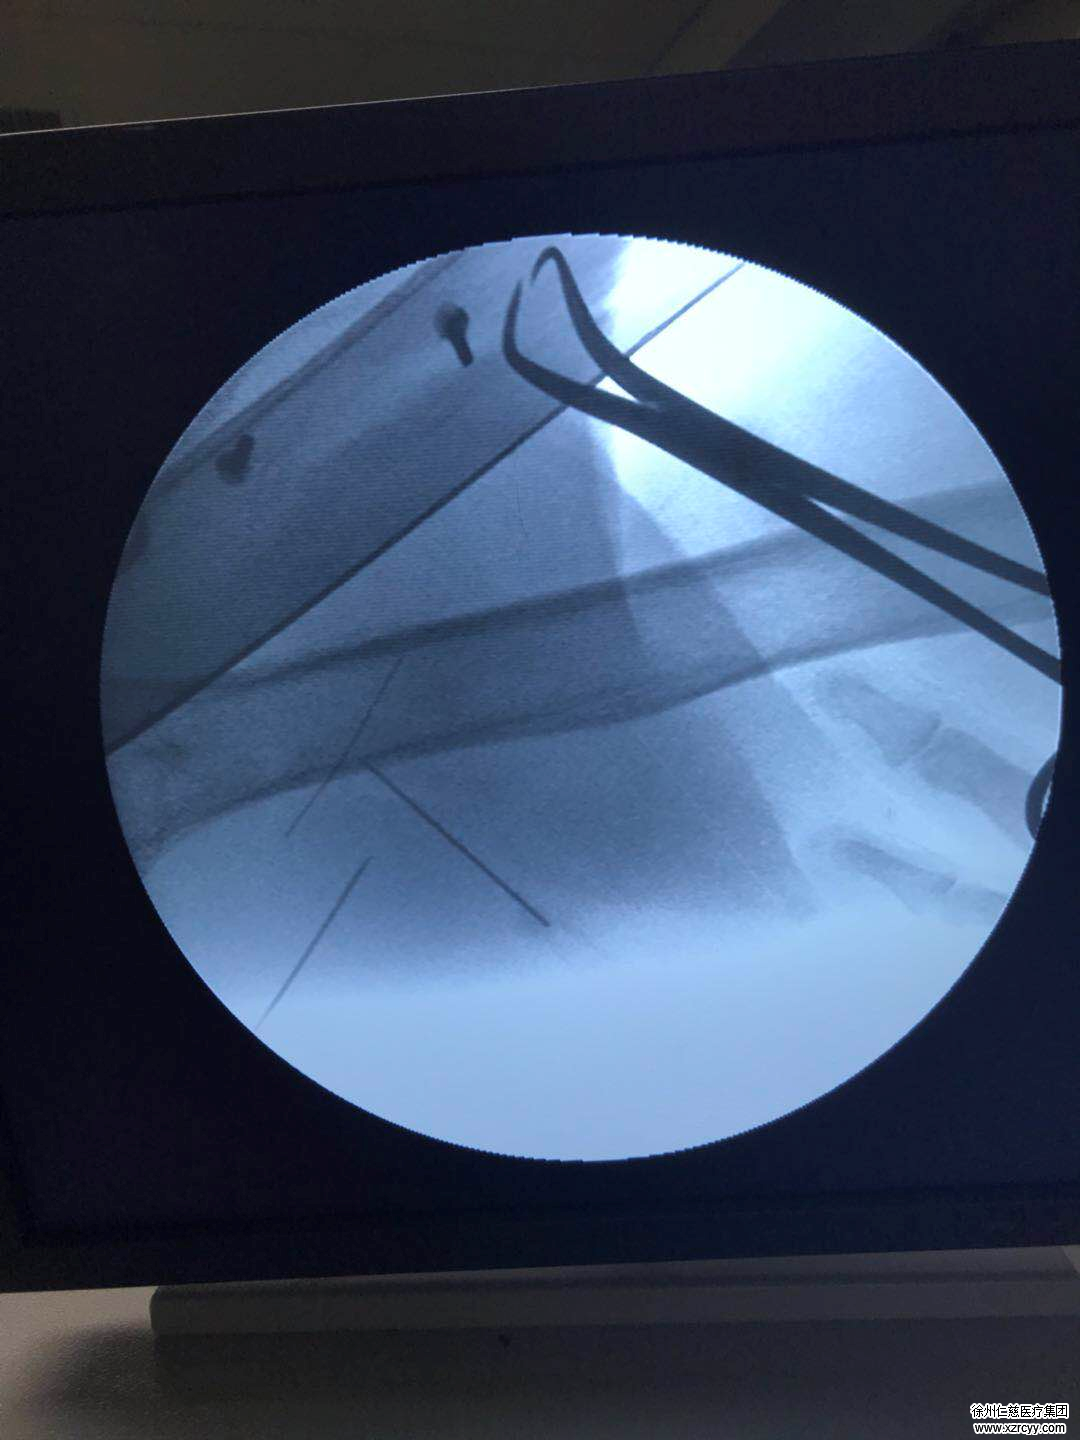

在betway在线登陆,手外科一病区主任李甲安排郑老太接受X线检查,结果发现,郑老太的左臂下侧针眼处已经形成血肿,而CR片子正中赫然显示郑老太的左臂下侧中有一根长约5厘米,跟注射器上的针头一样长的针灸断针!事不宜迟,李甲医生考虑到郑老太的年龄,且针灸用针又细又软,随着肌肉运动收缩,可能四处“游离”,犹如一颗小石子掉进沙堆,要准确“定位”断针位置很困难,因为郑老太刚做完检查与进手术室这个期间,断针都可能“移位”!

术中,李医生进行再次定位,因为针灸断针随着肌肉运动收缩,可能四处“游离”,只能按照解剖层次一点一点往下走,根据C型臂的定位,终于在距离定位点3cm的肌肉层内找到了这根惹事的断针!大家松了一口气,李甲主任随即迅速的拔出了这根惹事的断针。